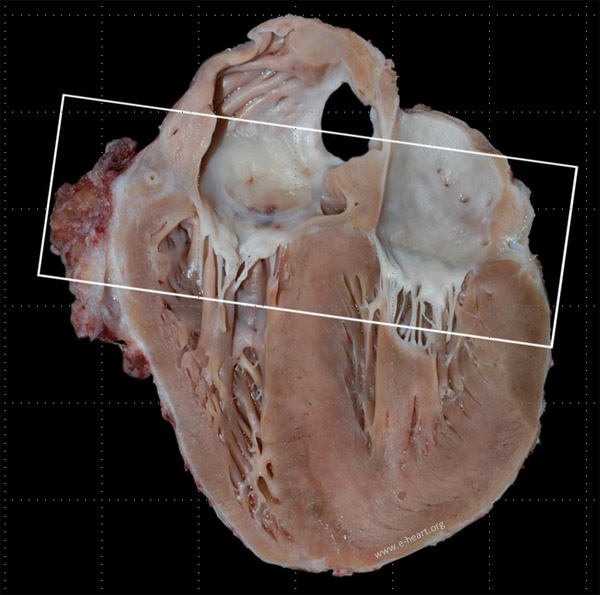

Allograft vasculopathy involves both epicardial and intramural coronary arteries.  The classic feature of CAV is that of diffuse concentric narrowing with luminal stenosis.  The images below show gross examination examples of allograft vasculopathy in a pediatric age heart.  The epicardial coronaries are markedly thickened.  Microscopic features of allograft vasculopathy are shown here.

This coronal four chamber view of the heart shows the circumflex and the right coronary arteries. Close up of the area framed by the rectangle.